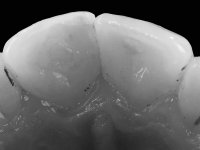

Paciente do sexo feminino, com 27 anos, não fumadora, apresentava uma restauração com resina composta tipo “Classe IV”, no angulo mesial do dente 2.1. A restauração não satisfazia esteticamente e fraturava com frequência. O bordo incisal do incisivo central direito e o remanescente natural do incisivo central esquerdo apresentava uma caracterização bastante marcada. Várias áreas de translucidez que tornariam a reabilitação bastante exigente sobre o ponto de vista técnico e estético. Na área da fratura não havia dentina exposta. A paciente gostava que a reabilitação tivesse uma abordagem o mais conservadora possível.

Realizou-se uma pré impressão em silicone para posteriormente ser feita uma restauração provisória em resina composta de polimerização “dual”. Seguidamente foi removida toda a restauração e realizado o preparo dentário. Este preparo consistiu na planificação do angulo dentário e na preparação ligeira da superfície palatina. A superfície palatina foi preparada para um assentamento sem interferências. Foi realizada uma impressão com dupla mistura e dupla viscosidade e de seguida foi feita uma restauração provisória em resina de polimerização “dual” sem qualquer tipo de adesão. Em laboratório, realizado o modelo de trabalho foi confecionada uma micro restauração de cerâmica feldespática. Essa peça de cerâmica utilizou essencialmente a superfície palatina mesial e o angulo incisal para se estabilizar. Na superfície vestibular a peça de cerâmica sobrepunha-se á superfície vestibular dentária em cerca de 2mm. Na clínica, a restauração provisória foi removida. A superfície dentária foi devidamente preparada e a micro restauração cerâmica depois de devidamente acondicionada foi colada no dente somente com adesivo. A superfície de cerâmica que sobrepunha a superfície dentária vestibular foi cuidadosamente eliminada. Para isso foi sendo feito o seu polimento de forma progressiva com discos e pontas de borracha.